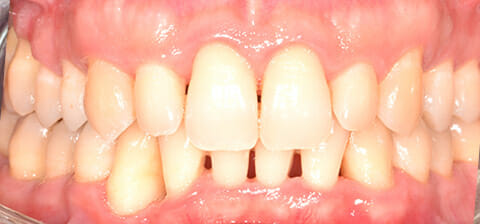

Il risultato ottenuto dalla terapia parodontale microbiologicamente guidata è stato il salvataggio di tutti gli elementi considerati da estrarre e l’abbassamento della carica batterica patogena.

Con terapia parodontale microinvasiva: si noti la ricrescita naturale dell’osso e del tessuto parodontale.